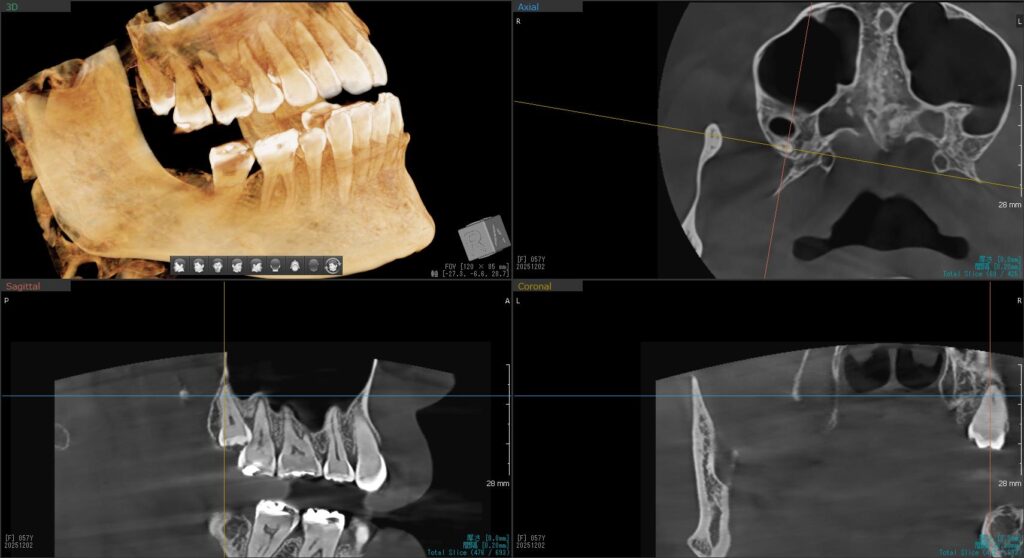

まず1人目の患者様。

年明けに予定していた右下の親知らずの抜歯を行いました。

左下の親知らずは一部が見えており、レントゲンで詳しく確認すると、手前の歯を押すように斜めに生えていました。

無事に抜歯終了!